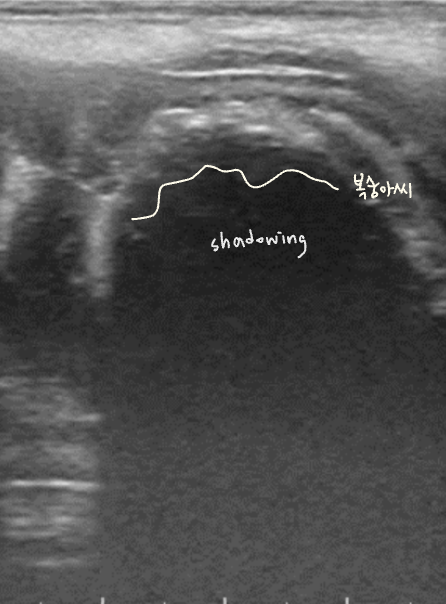

์ด๋ฌผ์ ์ด์ํ์์์ shadowing ๋ฐ์, ์์ฆ์ X-ray๋ณด๋ค ์ด์ํ๊ฐ ์ฐ์ ๋๊ธฐ๋ ํจ.

- ์์ ๊ธ์ฌ โ ์ ์์ธ์์ ์ด์ํ ๊ฒ์ฌ โ shadowing์ ๋ณด์ด๋ ์ด๋ฌผ์ ์ฆ๊ฑฐ ํ์ธ